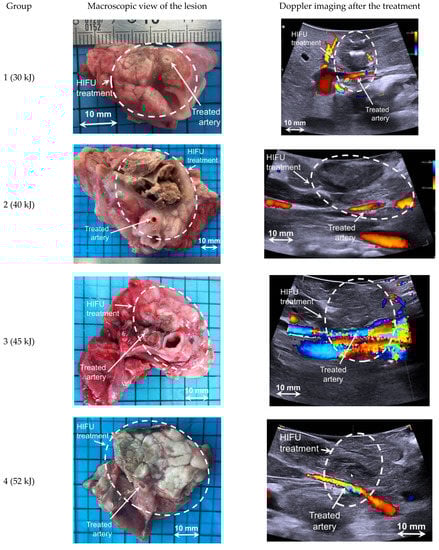

Figure 4.

Typical examples for each group of HIFU ablations observed macroscopically and on ultrasound imaging 14 days after treatment.

All treatments induced a lesion that was palpable and easily visible on ultrasound images and macroscopically appeared as a color change in the treated tissue (Figure 4). Treated tissues were harder than untreated pancreatic parenchyma and appeared as a hypoechoic region in the ultrasound images (Figure 4). The lesion dimensions were completely different for cystic and necrotic lesions (Table 2), but a high correlation was found between the dimensions measured on ultrasound images and the dimensions measured macroscopically in all cases (r = 0.82, p < 0.05).

Histological analyses confirmed that all treatments were homogeneous without any vessel occlusion. Histologically, HIFU ablation corresponded to coagulative necrosis, with a clear delimitation between treated and untreated pancreatic parenchyma (Figure 5). Arterial lesions were characterized by necrosis of the arterial wall, loss of endothelium, condensation of muscle fiber nuclei, disruption of elastic fibers, and necrosis of the outer elastic lamina and adventitia (Figure 6). Necrosis of the peri-arterial adipose tissue was also observed with accumulation of fibrin, small acute hemorrhages, and some neutrophils. Nerve bundles in the periphery of the artery were degenerated in groups 2–4, characterized by vacuolation of the nerve sheaths. These nerve lesions could explain the arterial spasms observed, leading to temporary stenosis. Moreover, these nerve lesions were also responsible for the loss of arterial vasoconstriction capacity, explaining how an artery experiencing an initial spasm could be treated several times thereafter without blood flow being further affected. Arterial necrosis was observed in the lesions in group 4, which was treated with an emitted energy of 52 kJ (Figure 6d). Histological analyses also indicated that plexus nerves around the peripancreatic artery were treated by HIFU in all cases with fibrous tissues observed fifteen days after the procedure (Figure 7).